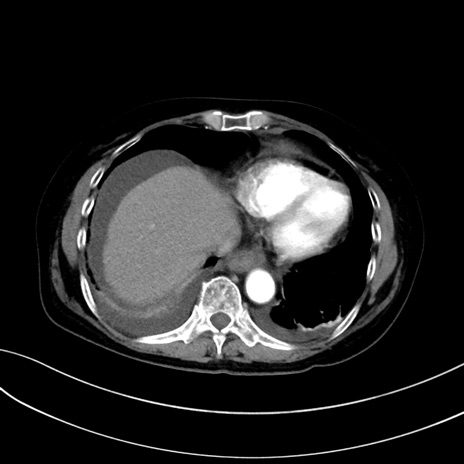

症例13 CT(横断像)1日半後